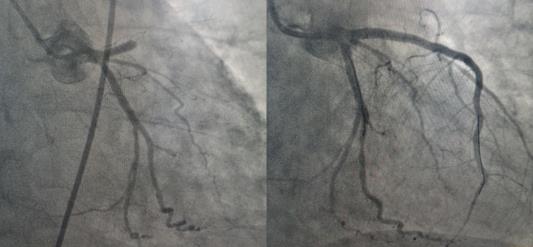

10:10患者到达延安大学咸阳医院,刚将患者从救护车推下进入门诊大厅,患者突然出现意识丧失,触摸大动脉搏动消失,心电监护提示室性心动过速,危急时刻,延安大学咸阳医院胸痛中心杨飞娟主治医师、谢昕护士、王丹丹护士协同泾阳县医院尹梦肖主治医师、张阳阳护士立即就地抢救,门诊梁田副主任医师及胸痛中心二线李新国主任也闻讯赶来支援。经过3次电除颤及胸外按压后患者恢复窦性心律,意识好转。在场医务人员立即将患者送至导管室,实施急诊PCI,于10:57开通闭塞血管,恢复血流,将危在旦夕的夏大叔从鬼门关抢救回来。目前患者正在进一步康复中。